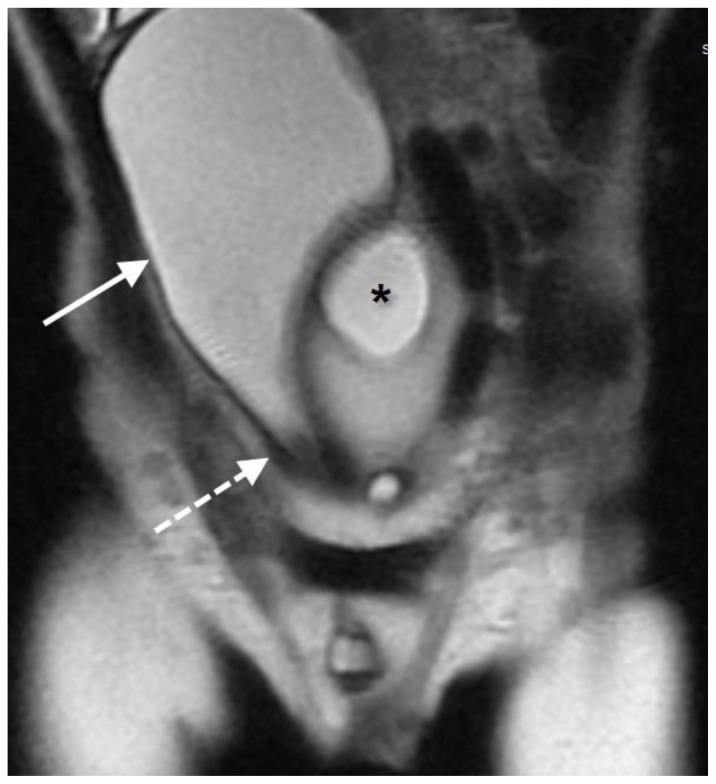

2-year-old male with an anorectal malformation and large anterior sacral meningocele. MRI of the pelvis performed on 1.5 Tesla GE Scanner.

FINDINGS: Coronal T2-weighted image of the lower abdomen and pelvis shows the elongated bladder (arrow) being displaced superiorly and to the right by the meningocele (*). The bladder neck (dashed arrow) is stretched and narrowed.

TECHNIQUE: T2 FSE Coronal, TE 100, TR 1171, slice thickness 4 mm